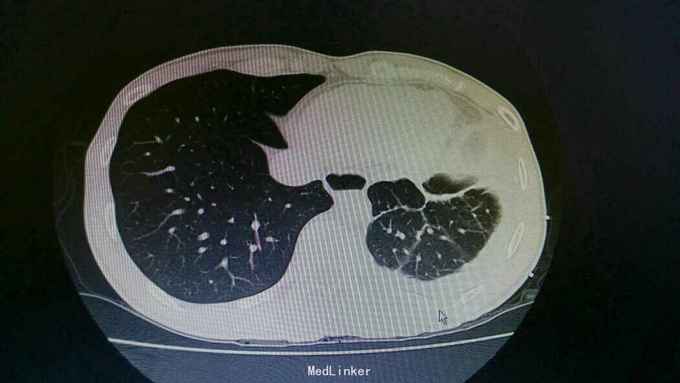

诊断:结核性胸膜炎 治疗:入院予以左侧胸水引流,T-SPORT A68,B24。予以四联抗结核治疗。辅查胸部CT患者左侧胸水减少,病情好转。